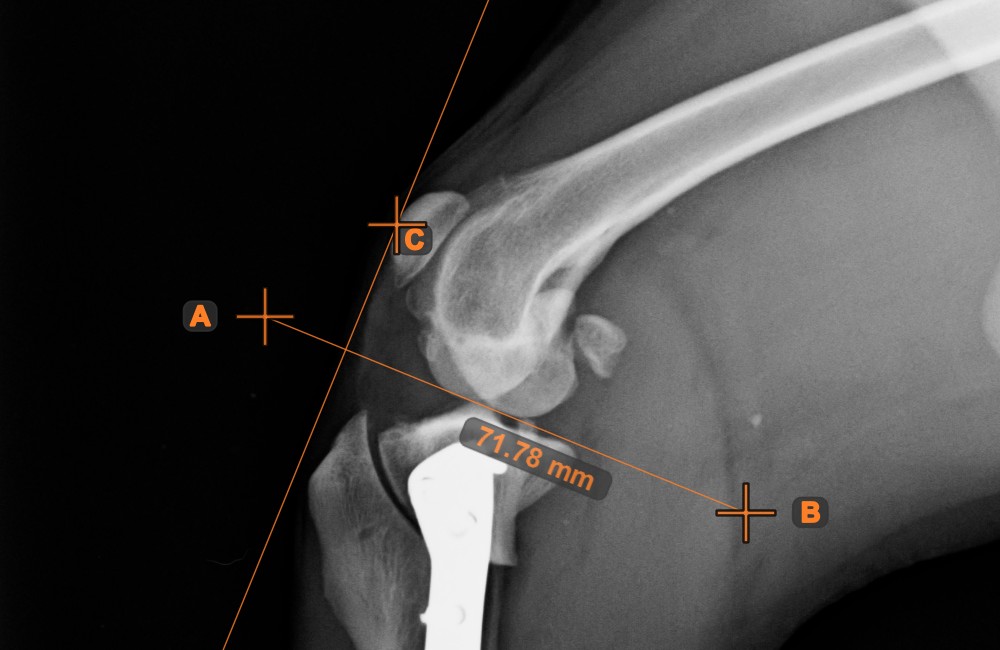

Abstand zwischen Linie und Punkt¶

Messen Sie den Abstand zwischen einer Linie und einem bestimmten Punkt in der Szene mit dem Werkzeug Abstand zwischen Linie und Punkt

.

Wählen Sie das Werkzeug aus der linken Symbolleiste aus und weisen Sie es einer der verfügbaren Maustasten zu. Beginnen Sie die Messung, indem Sie eine bereits vorhandene Linie in der Szene auswählen. Um die Messung abzuschließen, setzen Sie den gewünschten Punkt in der Szene oder wählen Sie einen bereits vorhandenen Punkt aus. Der Abstand zwischen der Linie und dem Punkt wird automatisch berechnet.

Ändern Sie die Messung, indem Sie einen der Punkte mit dem Werkzeug Objekt auswählen/verschieben

verschieben.